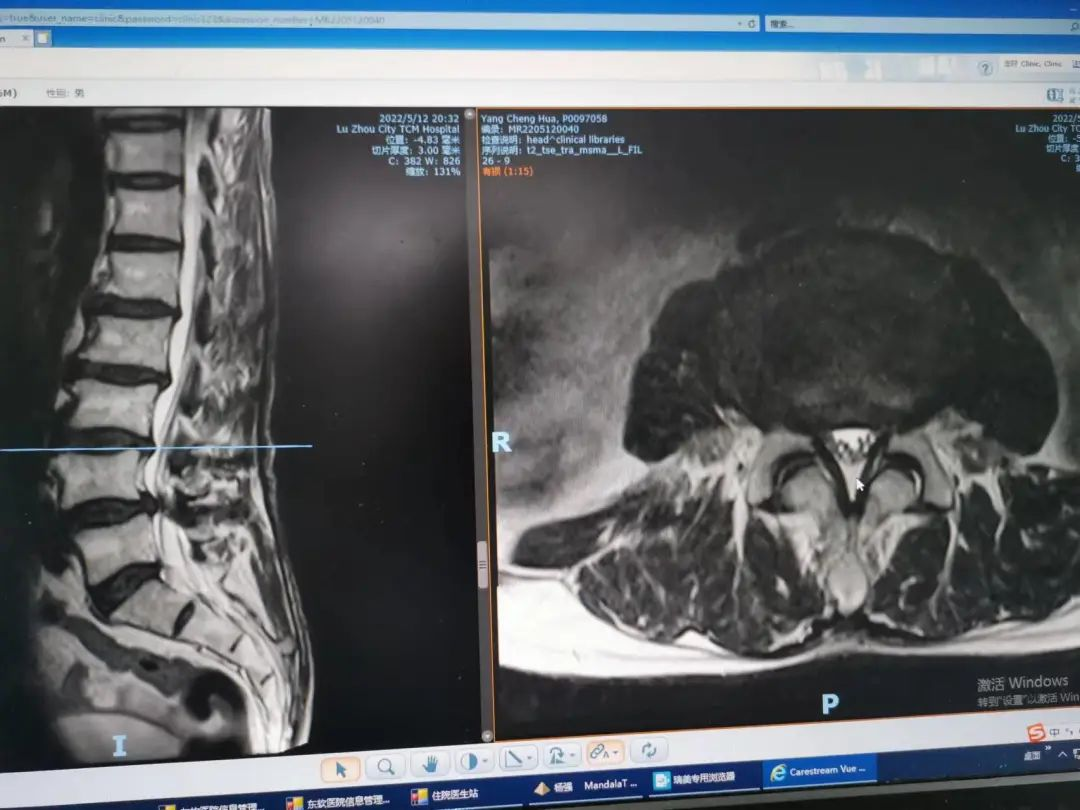

杨先生腰椎管狭窄症拍片

杨先生脊髓性颈椎病拍片